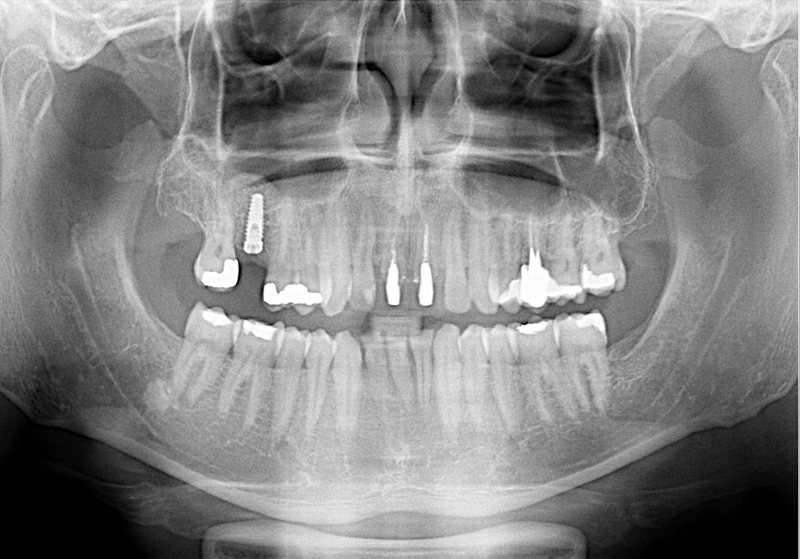

Při ztrátě molárů a premolárů v horní čelisti a jejich náhradě implantáty se často setkáváme s nedostatečnou vertikální nabídkou kosti pod čelistní dutinou, často doprovázenou i nedostatečnou horizontální nabídkou a sníženou kvalitou kosti

(v oblasti 2. premoláru v 50%, v oblasti moláru až v 80% případů nedostatečná kostní nabídka)

Od roku 1985 je tento problém řešen augmentační operací nazývanou sinus lift.

Jedná se o vyzvednutí membrány, která čelistní dutinu vystýlá, pod vyzvednutou membránou vznikne kapsa, kam se umístí augmentační materiál, do kterého se zavedou implantáty.

Vhojení implantátů se při této operaci prodlužuje na 6-12 měsíců.